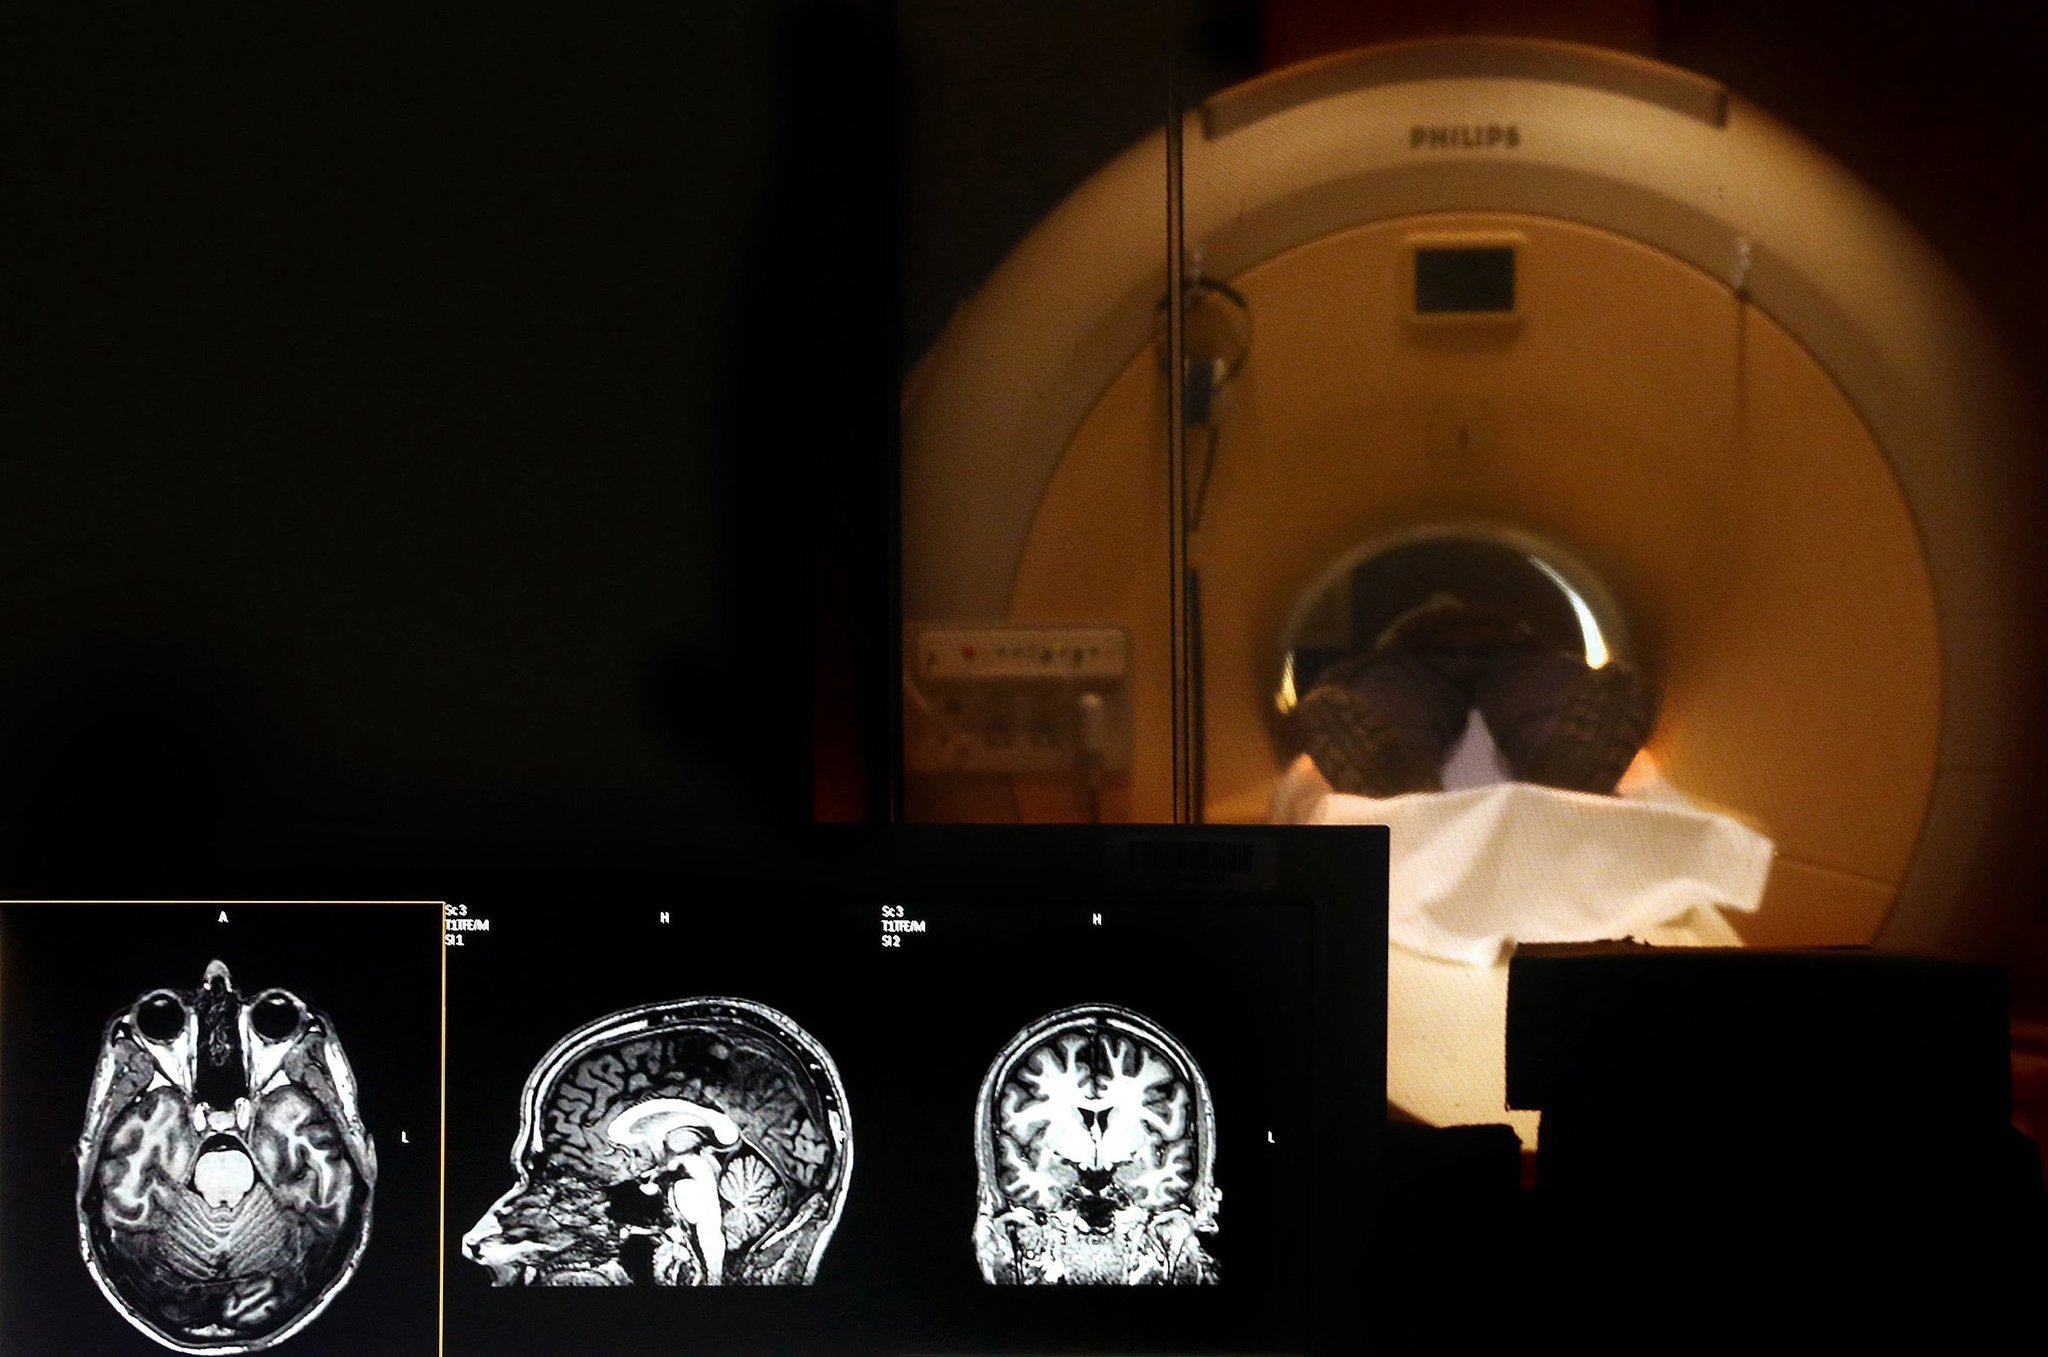

MRI机器使用强磁场产生身体器官的图像。因为强磁场,不允许有金属物体在MRI的房间。即使它是一个安全的程序,但是,如果不采取安全措施,可能导致严重的伤害。这是疏忽遵循严格的安全程序导致丸的死亡。

Rajesh丸的叔叔,要不是Solanki,告知Rajesh问一个初级员工携带的气缸内部和他向Rajesh保证机器了。”病房男孩请他帮助。他们说,这是好的。他接近了机器,而是把机器内的氧气缸。承担责任,而是医院工人骂我们Rajesh已经接近MRI机器与气缸在手里。”孟买警方已经逮捕了医生和初级员工的指控导致死亡由于疏忽造成的。病人应该接受MRI扫描,Laxmibai Solanki,仍然承认同一家医院。